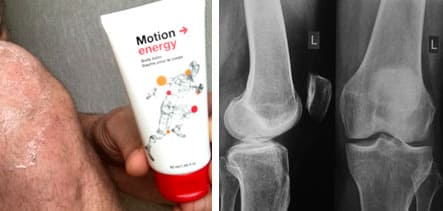

Así es cómo me enteré de Motion Energy . Por supuesto, ya había oído hablar del poder curativo del eucalipto, pero la verdad es que no creía mucho en él. Pero todo resultó muy simple: este gel es muy eficaz y fácil de usar. Puedes usarlo en el trabajo sin que nadie se dé cuenta. ¡Es asombroso! Le pedí a mi entrenador que me ayudara a pedirlo. Él me ayudó a comprar el gel con descuento, así que pagué solo la mitad del precio. Sale muy asequible para tener una buena salud.

El gel me llegó tres días después. Mis primeras impresiones fueron muy buenas: tiene una textura ligera y un agradable olor a eucalipto. Lo principal es que su fórmula solo contiene componentes naturales como aceites de eucalipto y canela y extracto de jengibre. Nada de sustancias químicas ni componentes sintéticos.